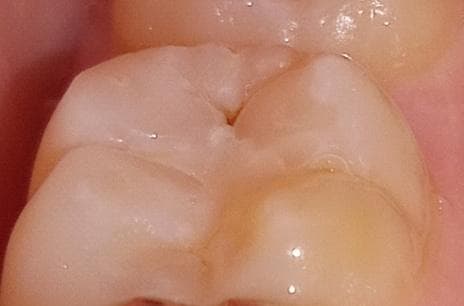

(첫번째 사진은 레진하고 며칠뒤에 찍은 사진이고

두번 째 ,세 번째 사진은 어제 찍은 사진이에요.)

빨간 동그라미 부분 첨이랑 달리 조금 벗겨졌는데.. 검갈색에 자국이 보여서요.

사진상으로는 잘 안보여도 실제로 보면 더 잘보여요 ㅠㅠ

글규 첨에 레진하고 거울 보니 저렇게 구멍난 부분이 있어서.. 며칠 뒤에 여쭤보니 활동멈춘 충치라고 제외하고 나머자 부분 해주셨다고..그러셨는데.. 저것도 그렇고.... ( 처음부터 말씀해주셨으면 레진안하고 경과 지켜봤을 텐데.. 전혀 아프지도 않았는데..)